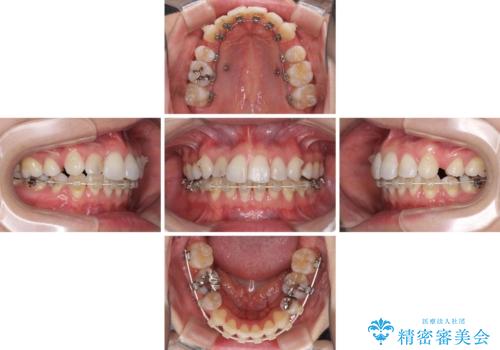

- ハーフリンガル

- 4年5ヶ月

治療期間の目安は3年~3年半でしたが、咬み合わせにより上顎のスペースがなかかな閉じきらず、治療期間が長期化してしまいました。